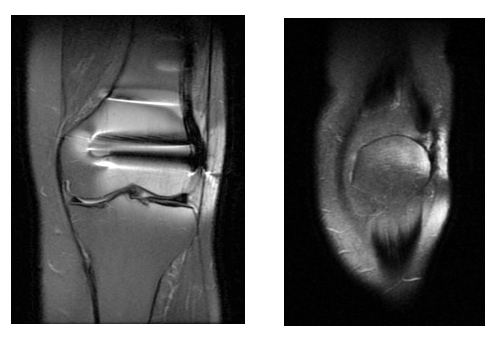

患者术前MR(显示软组织粘连,髌腱及股四头肌肌腱瘢痕增生)